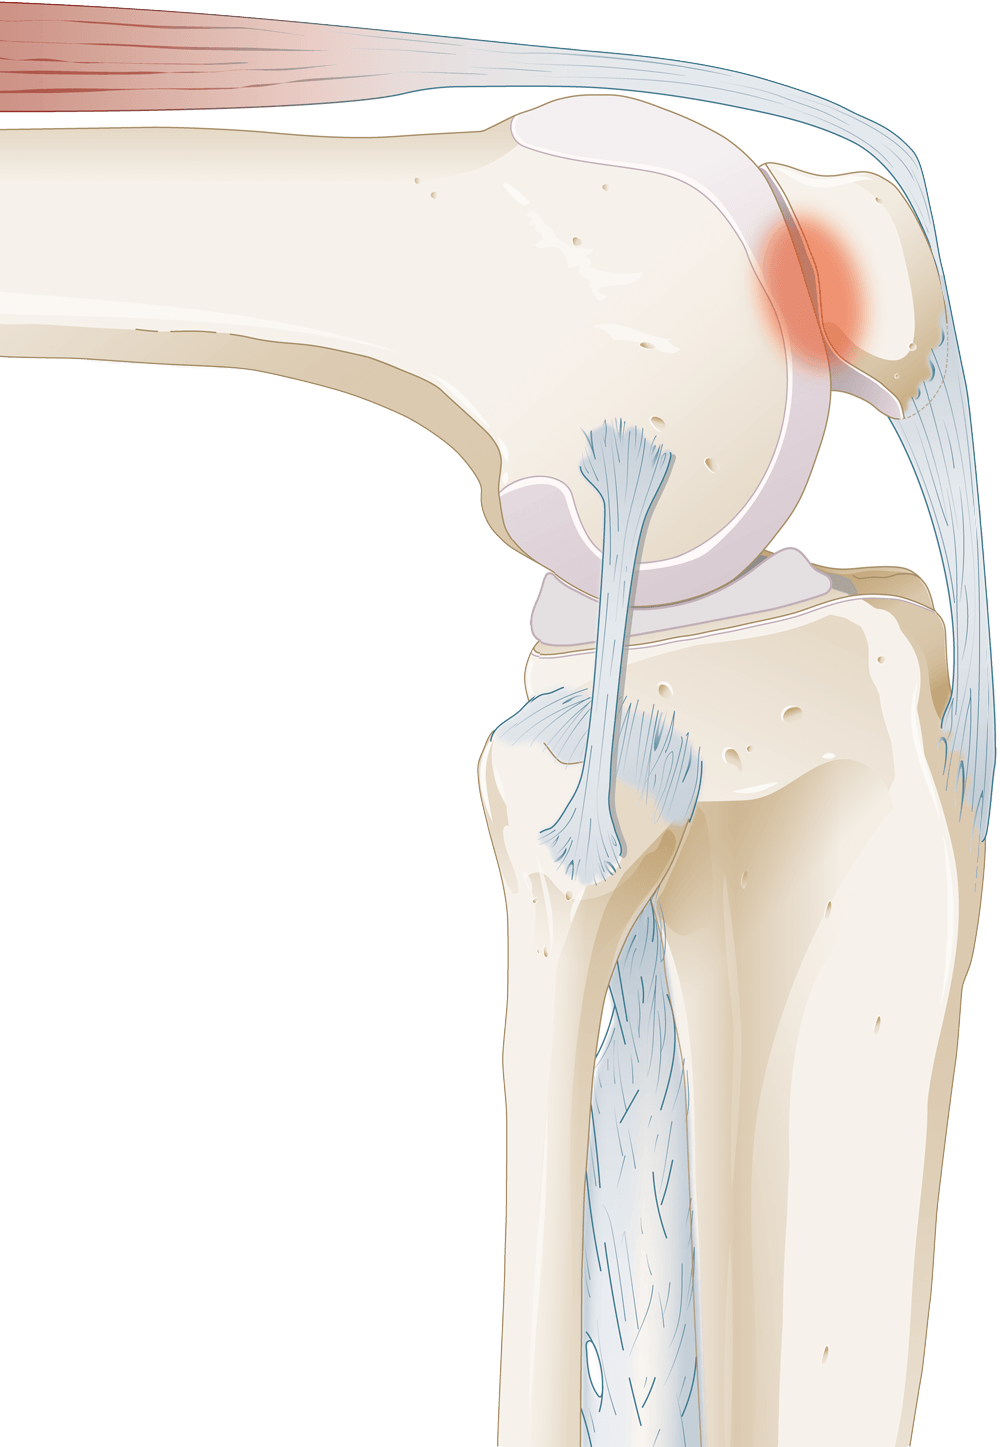

Bij patellofemoraal pijnsyndroom ontstaat pijn aan de voorkant van de knie, vaak door verhoogde druk tussen knieschijf en bovenbeen tijdens buigen en belasten.

Geïllustreerd door Karin Spijker

Het kan ook zijn dat er een bouwvariant bestaat van de knie, waardoor de knieschijf niet goed in het gootje van de knie (trochea) beweegt en hierdoor klachten kunnen ontstaan. Zo kan het zijn dat de knieschijf te veel naar buiten is geplaatst, dat het gootje van de knie te ondiep is, of dat de knieschijf te hoog staat.

Ten derde kan het zijn dat bij PFPS de spieren van het bovenbeen te weinig sterk zijn, of dat er een disbalans is ontstaan in de kracht van de verschillende bovenbeenspieren en dat hierdoor veranderde druk achter de knieschijf is ontstaan. Deze redenen achter PFPS worden tijdens een consult bevraagd en er wordt eventueel onderzoek gedaan naar de status en positie van de knieschijf en het gootje achter de knieschijf. Ook kan het zijn dat er een krachttest wordt geadviseerd om de kracht van de bovenbeenspieren in kaart te brengen.